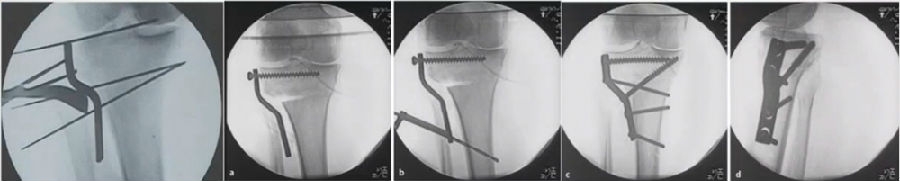

3Hybrid CWHTO

矫正角度过大,可采用Hybrid CWHTO,改变截骨合页点,有效避免CWHTOOWHTO的缺点。

混合截骨

典型病例,女性,56岁,农民右膝内翻18度。

术前影像

术中影像

结合影像学来看,该患者单纯用闭合截骨或开放截骨,对肢体均有影响,所以决定采用混合型截骨。术中混合截骨旋转中心选在内外1/3处,先做闭合楔,然后顺势将开放楔敲开,达到术前设计的目标力线。术后随访力线达到要求。

术后X线